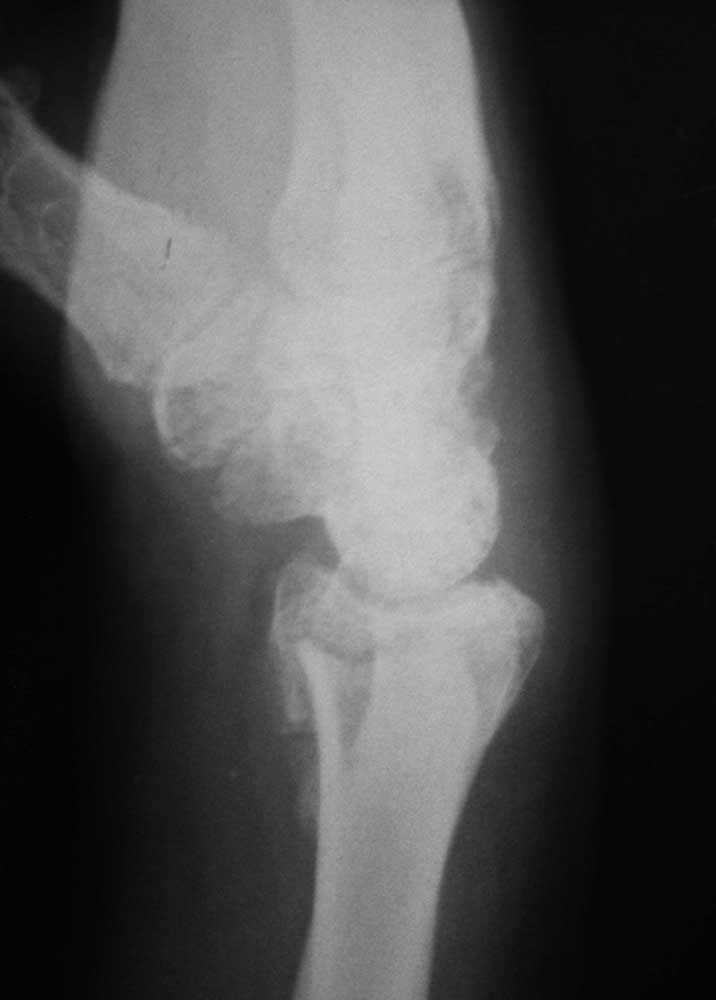

Re: Перелом дистального луча

То же самое, только в профиль